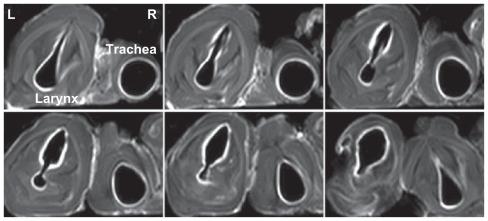

Various cationic liposome formulations were compared for their stabilization effects on the droplets containing gadobenate dimeglumine. The liposomes composed of egg phosphotidylcholine, cholesterol, and sterylamine in a molar ratio of 1:1:1 were found to enable the most efficient nebulization and the resulting droplet sizes were narrowly distributed. They also resulted in the most even coating on the laryngeal and tracheal lumen surfaces and produced significant contrast enhancement along the mucosal surface. Such contrast enhancement could help clearer visualization of several disease states, such as intraluminal protrusions, submucosal nodules, and craters.

This lipid-stabilized magnetic resonance imaging contrast formulation may be useful for improving mucosal surface visualization and early diagnosis of disease originating in the mucosal surfaces of the larynx and trachea.